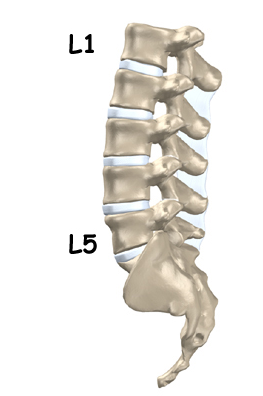

While carrying out activities such as daily chores, working, running errands, or taking care of children, maintaining good posture may be the last thing on a person’s mind. However, neglecting your posture could lead to health problems over time. There are specific muscles in the body, known as postural muscles that help keep the body upright. Bad posture may lead to overstretching of some muscles, while others may become stiff and tight. When standing, bending, or lifting objects improperly or slouching while sitting, postural muscles begin to overwork. If this happens, muscle pain and joint damage may develop.

Research shows that a large number of people suffer from back pain as a result of bad posture.

People who work in certain fields may also be more susceptible to health problems due to poor posture. Individuals working in professions that often require a lot of movement, standing for long periods, bending, and repetitive lifting, often suffer from low back pain as a result of bad posture. For instance, individuals who have high intensity jobs in nursing or construction. Research shows that when individuals in these professions receive specialized training (e.g., physical therapy) and education regarding how to maintain proper posture while working, the incidence of back pain drastically decreases.